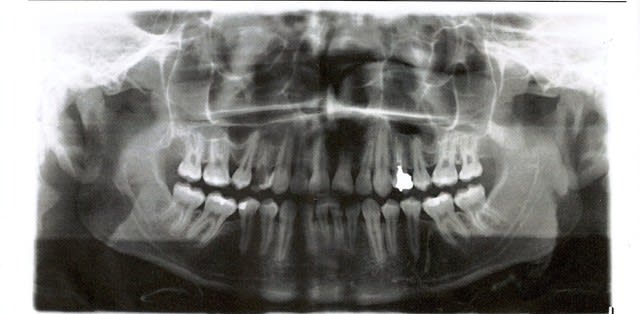

or je vous laisse voir la belle 14 , et même la 24 que je découvre

je pense de toutes façons faire l 'endo de 14 et couronner les deux, mais le pronstic n est pas terrible.. non?

c'est quoi l'image en distal de 35 ??????

Bon sa 14, elle est foutue évidemment. Sa 24 aussi à moyen terme.

Appel à l'ortho pour savoir s'il peut rebaguer pour virer les 4 et tout remésialer, ou alors voir avec les parents pour 2 implants.

16 ans est un peu jeune pour implanter... Croissance pas terminée... faut temporiser avec du provisoire ou du bridge collé jusqu'à la fin de sa croissance...

rebaguer mais faut revoir la motiv du patient et celle de l'ortho alors que le traitement n'est pas ou plus stable. Le patient a t'il bien suivi son traitement ortho et ses RDV ? Parce que l'ortho pour laisser se développer de belles lésions carieuses comme celles là, ne devait pas aimer le patient ou ne jamais le voir...

on ne lui aurait pas extrait les 36 et 46 par hasard? Oui je sais 16 ans c'est un peu jeune pour avoir des 8 à quasi maturité , mais l'espace en distal des 35 et 45 et les morphos m'évoquent bien ça.

Tu as raison on a l'impression qu'il manque les 6 (les 4)

Quant au ttt ortho, vu la racine de la 21 et des 41-31 sur la radio, faut peut-être s'arrêter là.